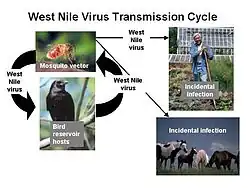

An example of this vector-host relationship can be observed in the transmission of the West Nile virus. Female mosquitoes of the genus Culex prefer to consume the blood of passerine birds, making them the hosts of the virus.[17] When these birds are infected, the virus amplifies, potentially infecting multiple mosquitoes that feed on its blood.[15] These infected mosquitoes may go on to further transmit the virus to more birds. If the mosquito is unable to find its preferred food source, it will choose another. Human blood is sometimes consumed, but since the West Nile virus does not replicate that well in mammals, humans are considered a dead-end host.[16][18]